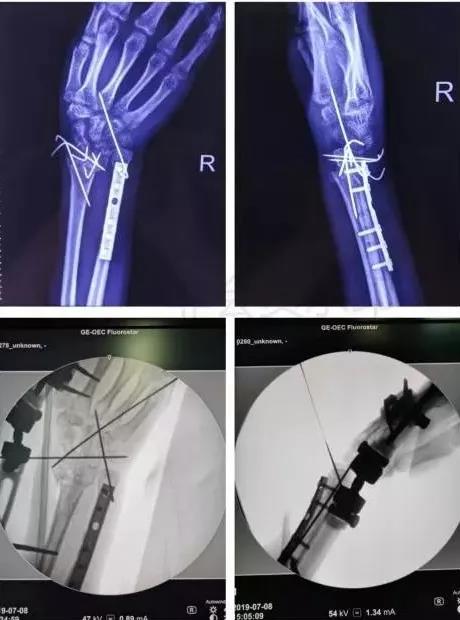

5)前臂骨折(尺骨,桡骨,或双骨折)

- 闭合或开放性骨折均争取伤后6-8h完成。

- 手术后延,尺骨-桡骨骨桥形成风险概率高。